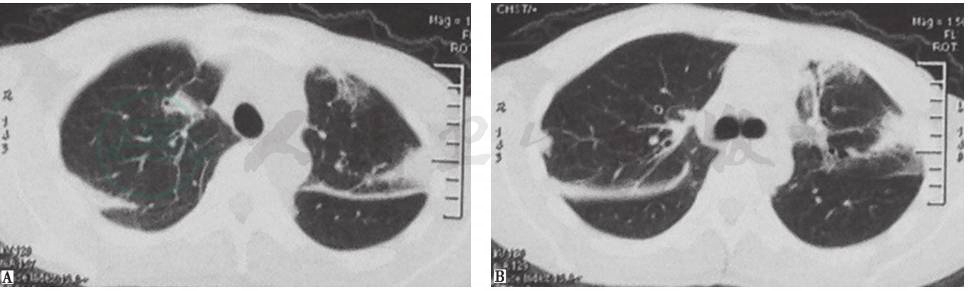

2013年1月4日查胸部CT,见双肺多发实变影,其间可见支气管充气征,伴左侧少量胸腔积液 (图1)。

图1 胸部CT表现(2013-01-04)

患者入院进行抗感染治疗(阿莫西林克拉维酸、亚胺培南西司他汀)10天后,复查胸部CT(2013年1月14日),提示双肺原有实变病灶较前(2013年1月4日)略有进展(图2)。

图2 入院治疗10天后复查胸部CT表现